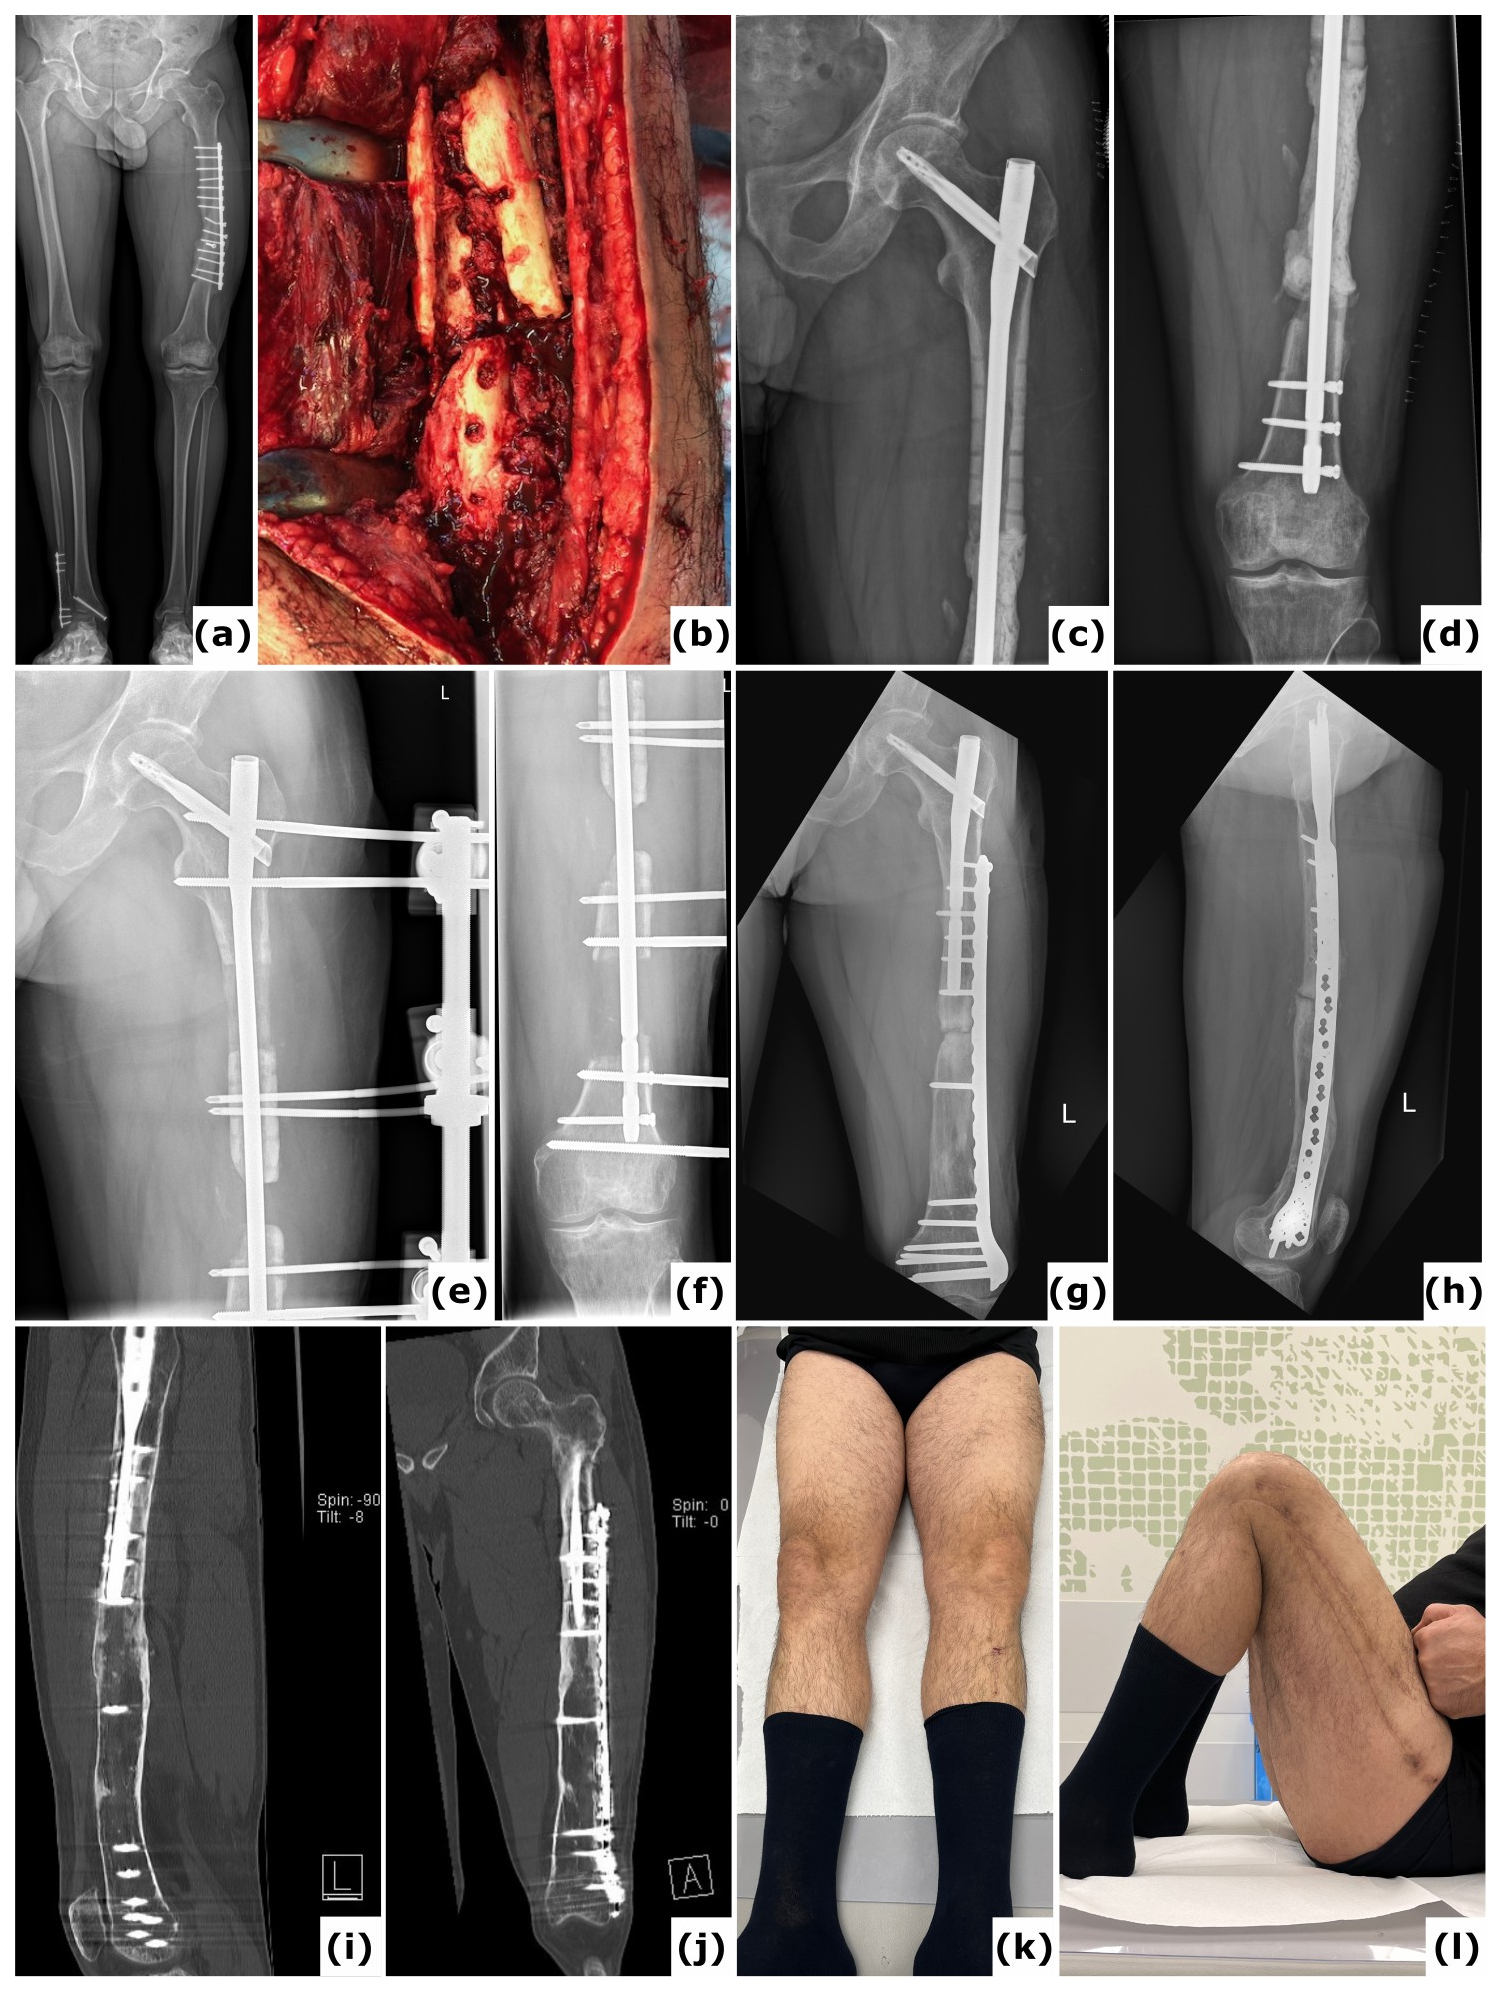

Figure 5Trifocal transport over a nail. A 44-year-old patient presented with a fracture-related infection of the femur following plate osteosynthesis. (a) A long-leg radiograph obtained 6 months after the initial procedure at another institution shows an unhealed fracture and failure of the osteosynthetic construct. (b) An intraoperative clinical image displays the comminuted (avascular) fracture site. Cultures identified Staphylococcus epidermidis. (c–d) Anteroposterior radiographs of the left femur taken postoperatively reveal a large segmental defect, treated with an intramedullary nail and a PMMA spacer. (e–f) Anteroposterior radiographs document progression of the bone transport. (g–h) One-year anteroposterior and lateral radiographs demonstrate removal of the external fixator and revision to a nail/plate construct; cultures from this surgical intervention were negative. (i–j) Computed tomography (CT) images at 2 years confirm consolidation at all sites. (k–l) Clinical images at 2 years illustrate a full range of motion in both lower extremities.